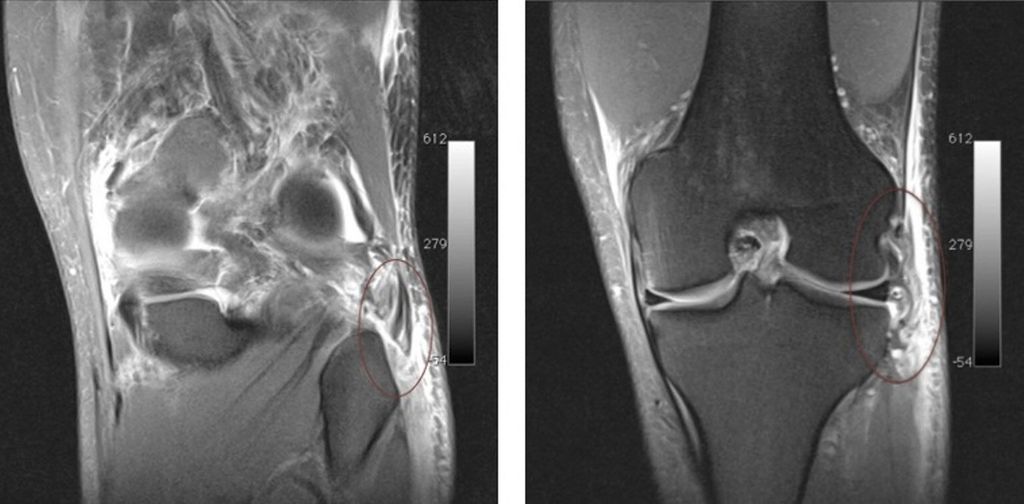

Eine MRT-Kontrolle nach 18 Monaten zeigte ein unauffälliges Transplantat (Abb. 4). Bei der postoperativen 2-Jahres-Kontrolle hatte der Patient keine Instabilität, er konnte wieder auf Leistungsniveau Fußball spielen (Abb. 5).

Abb. 5: Bei der postoperativen 2-Jahres-Kontrolle hatte der Patient klinisch keine Instabilität sowie eine normale Kniegelenksfunktion unter Maximalbelastung und konnte wieder auf Leistungsniveau Fußball spielen